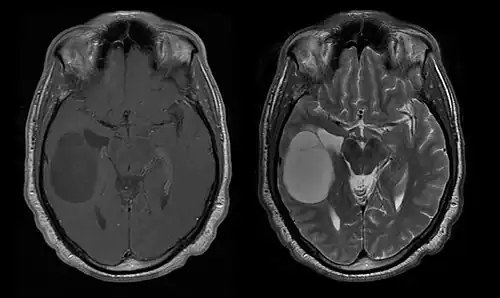

Durch Computertomographie (CT) und Kernspinresonanztomographie (MRT) kann eine Neoplasie im Gehirn effektiv nachgewiesen werden. Zur Identifizierung von Läsionen ist die MRT empfindlicher als die CT, weist aber für Patienten mit Herzschrittmachern, inkompatiblen Prothesen, Metallklammern und anderem Kontraindikationen auf. Die CT bleibt die Methode der Wahl, um Verkalkungen innerhalb der Läsionen oder Knochenerosionen der Schädeldecke oder -basis zu erkennen. Die Verwendung von Kontrastmitteln, die im Fall der CT jodiert und im Fall der MRT paramagnetisch (Gadolinium) sind, ermöglicht die Erfassung von Informationen über die Vaskularisation und Integrität der Blut-Hirn-Schranke, eine bessere Definition der Tumorgeschwulst im Vergleich zum umgebenden Ödem und die Erstellung von Hypothesen über den Grad der Malignität. Die radiologische Untersuchung ermöglicht auch eine Bewertung der mechanischen Auswirkungen und die daraus resultierenden Veränderungen der Gehirnstrukturen, die sich durch den Tumor ergeben, wie zum Beispiel Hydrocephalus und Hernien, deren Auswirkungen tödlich sein können. Schließlich kann mit dieser Diagnostik in Vorbereitung einer Operation der Ort der Läsion oder die Infiltration des Tumors in lebenswichtige Bereiche des Gehirns bestimmt werden. Zu diesem Zweck ist die MRT effizienter als die CT, da sie dreidimensionale Bilder liefern kann.[4]

Diagnostische radiologische Bildgebungsinstrumente heben die Veränderung des neoplastischen Gewebes im Vergleich zum normalen Gehirnparenchym hervor (durch Änderungen der elektronisch dargestellten Dichte des Gewebes bei der CT und der Signalintensität bei der MRT). Wie die meisten pathologischen Gewebe sind auch Tumoren durch eine erhöhte Ansammlung intrazellulären Wassers erkennbar. Im Computertomogramm erscheinen sie hypodens, das heißt von geringerer Dichte als das Gehirnparenchym, im Kernspinresonanztomogramm bei Spin-Gitter-Relaxation hypointens und bei Spin-Spin-Relaxation sowie Protonengewichtung (PD) hyperintens.[5][6]

Die Computertomographie des Gehirns zeigt typischerweise eine Gewebsmasse, die entweder durch Kontrast verstärkt werden kann. Bei der CT erscheinen niedriggradige Gliome normalerweise isodens zum normalen Parenchym und zeigen daher möglicherweise keine Kontrastverstärkung. In ähnlicher Weise sind Läsionen in der Fossa cranii posterior, der hinteren Schädelgrube, im CT schwer zu identifizieren. Folglich sind die Ergebnisse einer solchen Tomographie allein nicht immer für diagnostische Zwecke ausreichend.[4] In zweifelhaften Fällen ist die Verwendung der empfindlicheren Kernspintomographie unerlässlich.

Auf -Kernspintomogrammen erscheint ein intrakranieller Tumor als massive Läsion, die nach Verwendung des Kontrastmittels lumineszierender werden kann. Eine Signalanomalie gibt es jedoch immer in -Kernspintomogrammen, die auf das Vorhandensein einer Neoplasie oder eines vasogenen Ödems hinweist. Normalerweise ist eine stärkere Lumineszenz (Kontrastverstärkung) ein Hinweis auf einen Tumor höheren Malignitätsgrades. Ein Kontrastring ist charakteristisch für ein Glioblastom, wobei der Lumineszenzanteil dem lebenswichtigen Teil des bösartigen Tumors und der dunklere -hypointense Bereich der Gewebenekrose entspricht.[4]